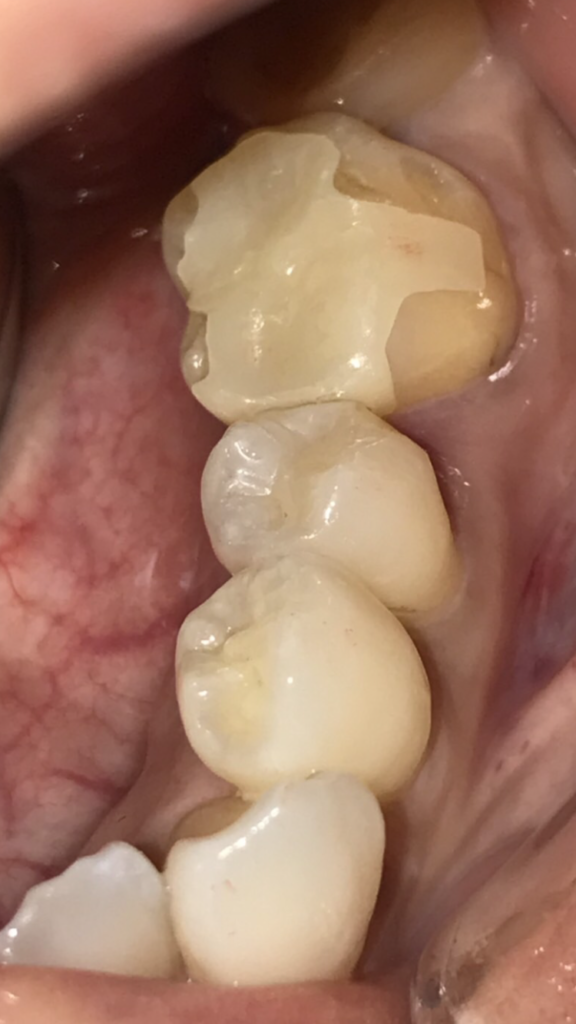

銀歯を外し、虫歯をとった時の写真です。欠損した部分のみをダイレクトボンディングにて修復しました。

ダイレクトボンディングはコンポジットレジンと呼ばれるプラスチックを強化したものを充填するため、強度を考えるとセラミックやゴールドのほうが高いですが、歯を大きく削らずに残存歯質に色調を合わせて修復できる点ではメリットが大きいと思います。

残存歯質がある程度あり、強度が確保できる場合は治療時に提案させていただいております。